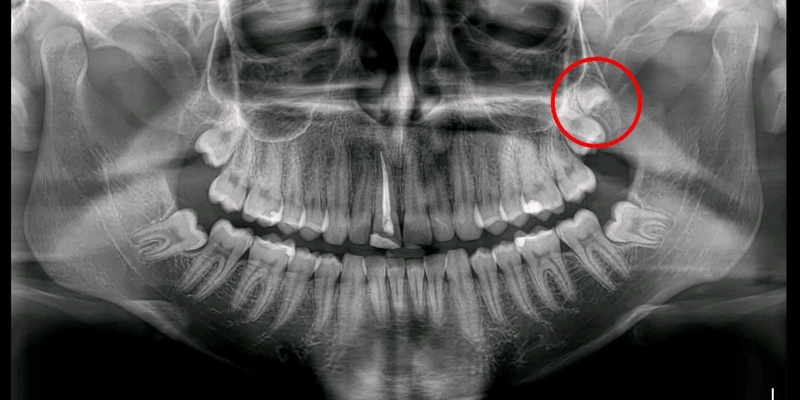

Bước 1: Thăm khám và chụp phim X-quang

Bác sĩ sẽ khám tổng quát, sau đó chỉ định chụp phim X-quang để đánh giá chính xác hình dạng, kích thước, hướng mọc của răng khôn và mối tương quan với các cấu trúc giải phẫu quan trọng.